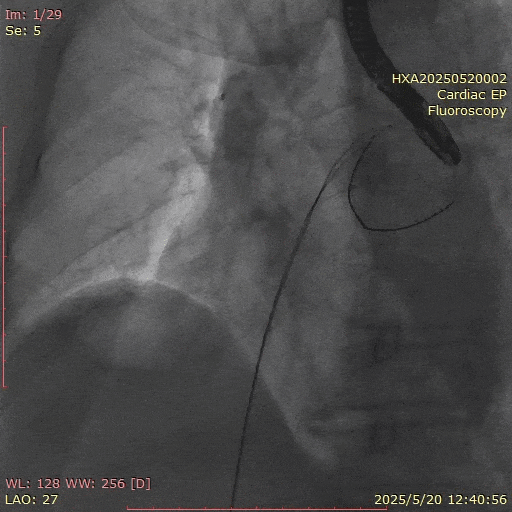

在经股静脉途径的TEER手术时,房间隔穿刺是一个很重要的基础步骤。有时候房间隔组织较韧较厚(多见于房间隔短穿刺位置需要靠后,或者外科房间隔修补术后),穿刺针通过之后要通过导引大鞘(GC)存在着较大困难,若强行推送大鞘可引起房间隔撕裂到左心房顶引起灾难性心包填塞。传统做法时使用外周球囊对房间隔进行扩张,但是不是每个导管室都常规配备外周球囊,且使用过大球囊仍可引起房间隔撕裂风险。我们提供了一种更简洁的方式,即使用导引鞘内芯和房间隔穿刺鞘两个管子(双管齐下)同时扩张房间隔穿刺口,再推送导引大鞘通过房间隔,无需额外器械,操作简单高效且安全(图1-4)。

图3. 沿着两根加硬导丝送入导引鞘内芯和房间隔穿刺鞘对房间隔进行扩张